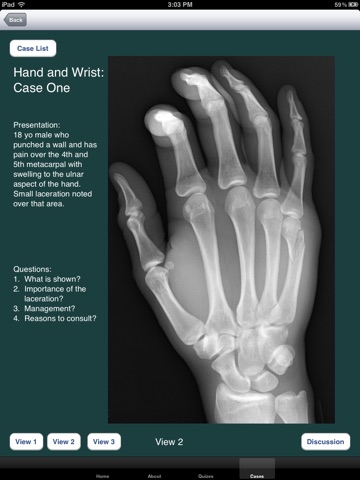

The application is one to use to learn skills related to the emergent-based diagnosis and care of orthopedic injuries. There are online tests associated with the application in order for a learner or instructor to gauge pre/post knowledge base, identify weakness, and measure competence. Some of the goals behind the app include: learning interpretation of plain films, appropriate care of orthopedic injuries, diagnosis and care of associated injuries, teaching management strategies, and uniform means of assessment through the online testing.